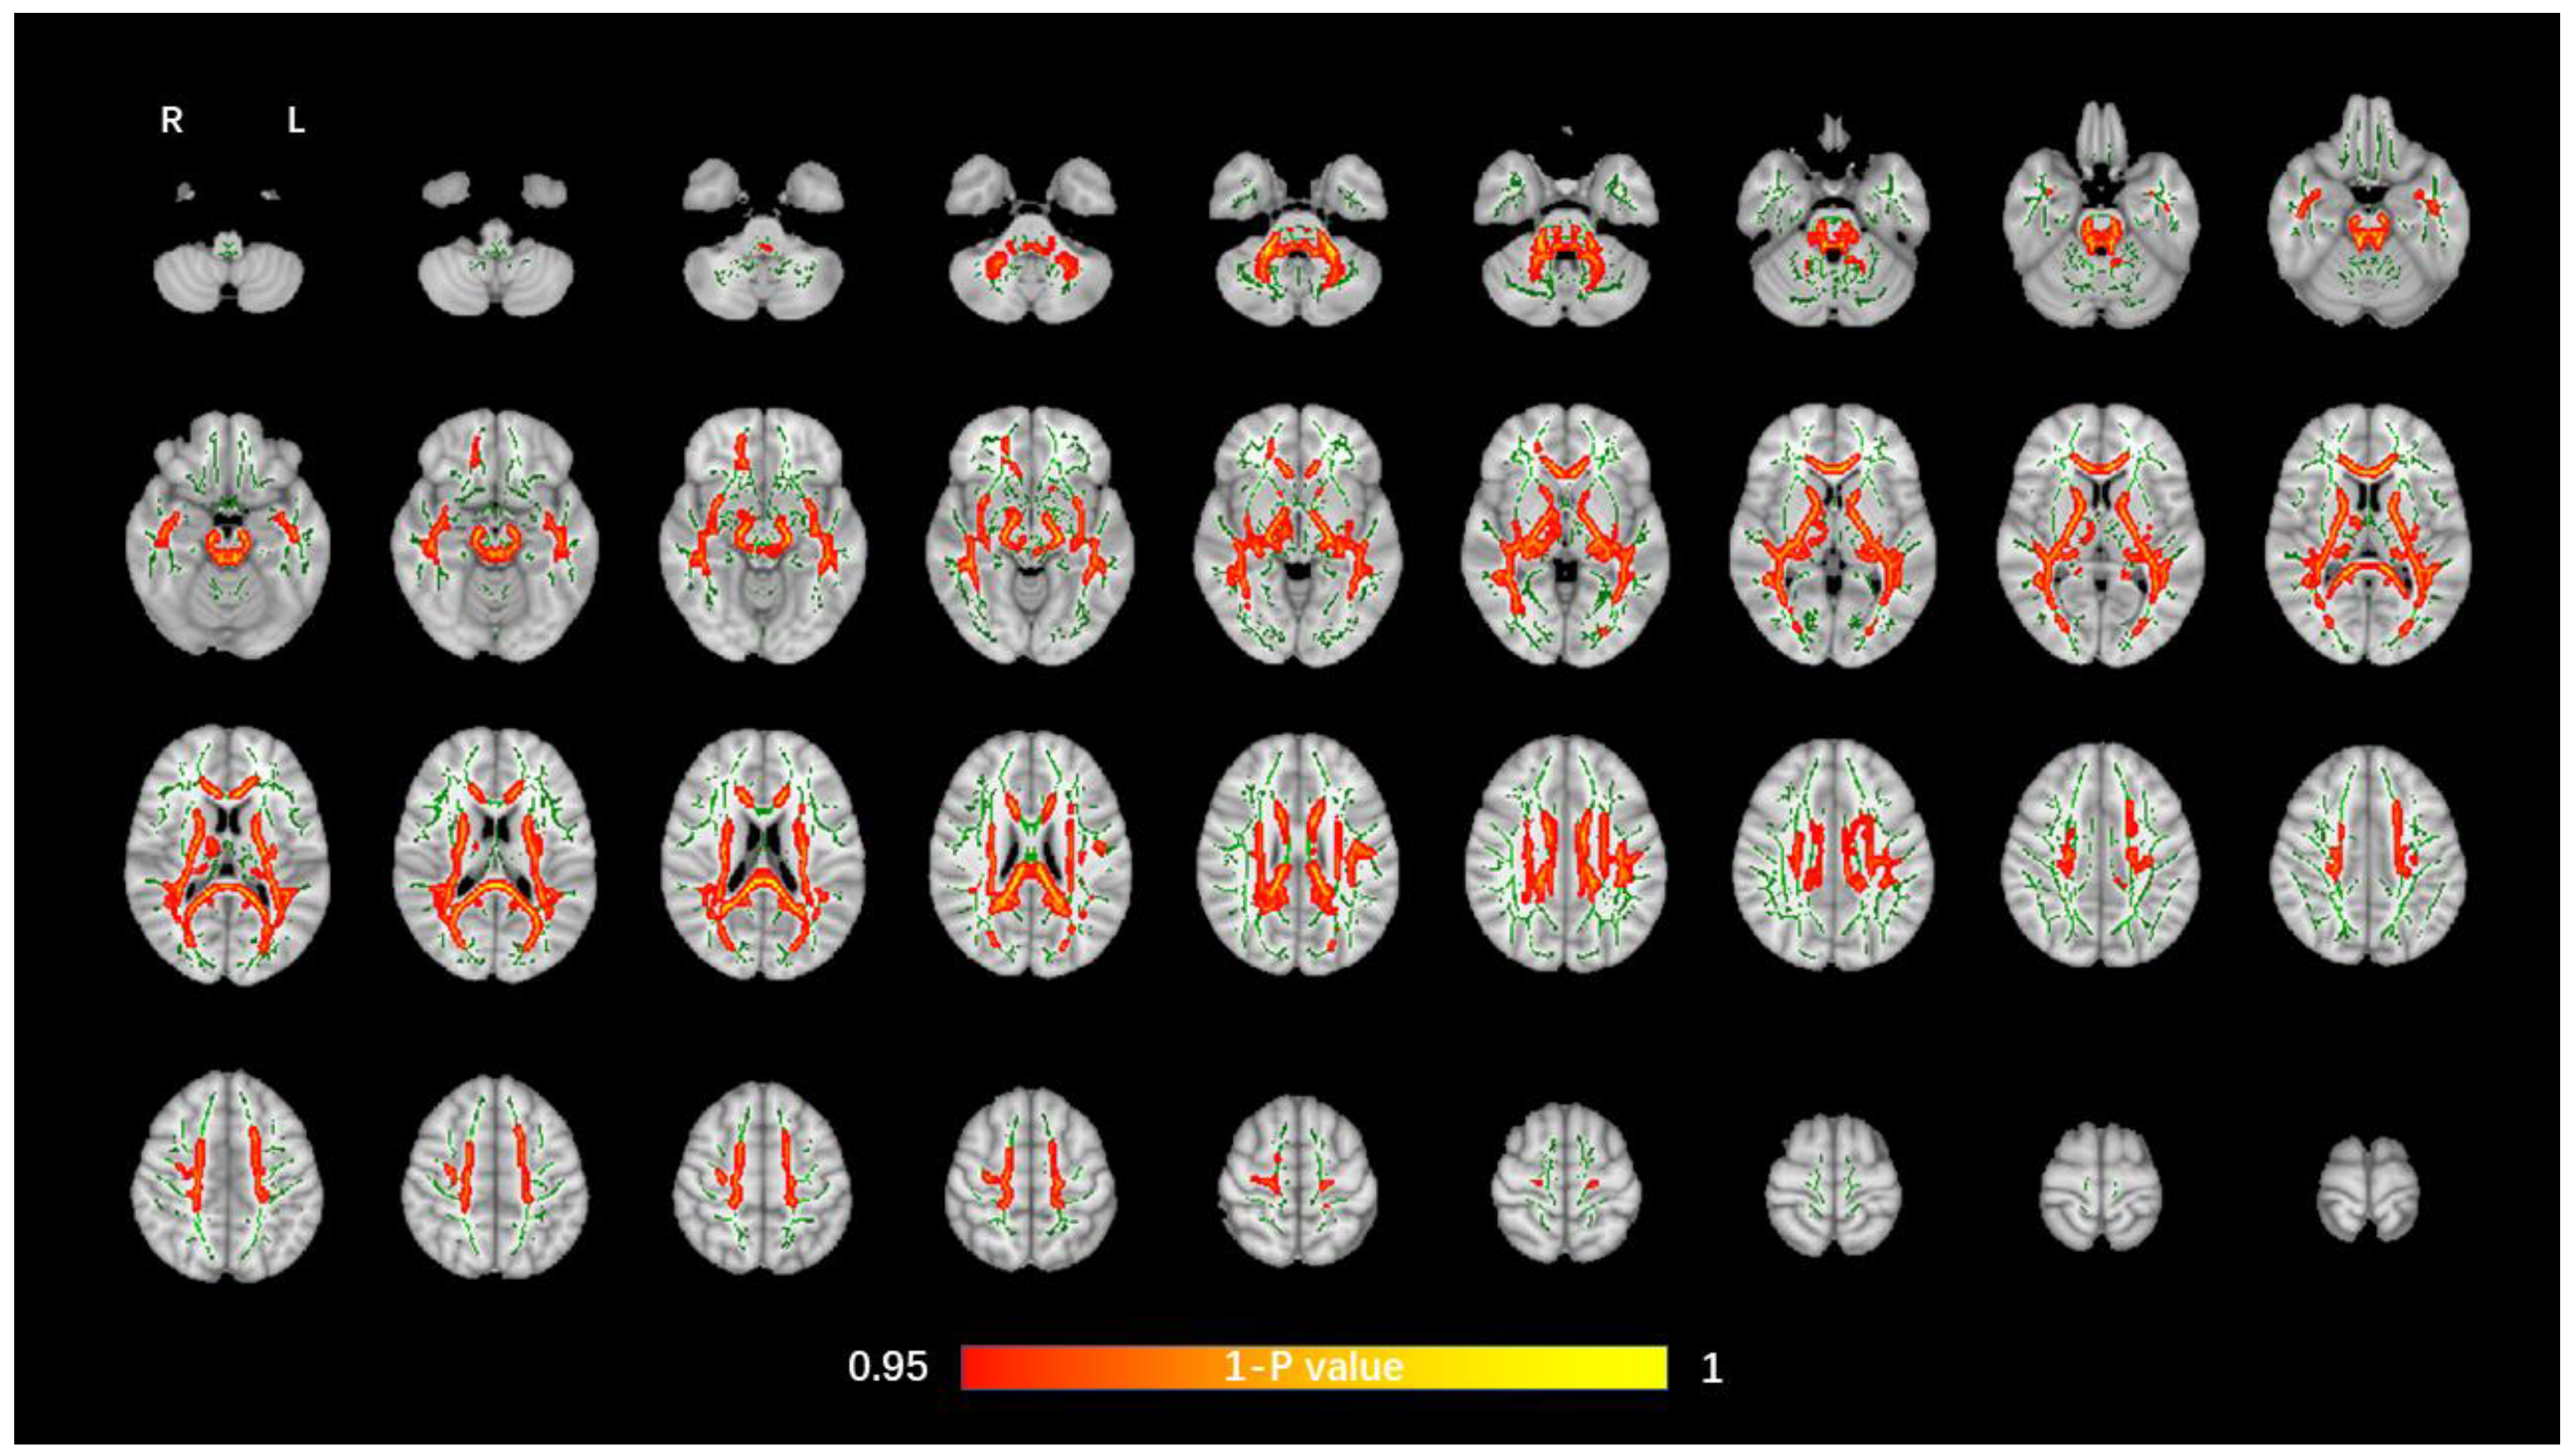

The average FA WM skeleton of all subjects was constructed in TBSS analyses, as shown by the green line in Figure 1, Figure 2, Figure 3 and Figure 4. An analysis of variance of voxel level was carried out on the WM skeleton, and the differences among the three groups were compared. p < 0.05 after FWE correction based on TFCE was statistically significant. Statistically significant areas were expanded to better show the position of WM fiber bundles, as shown in the red part in Figure 1, Figure 2, Figure 3 and Figure 4. The statistical results showed that the DTI indexes of most fiber bundles were statistically significant. There was a significant statistical difference in the FA, MD, AD, and RD values of the FMI, FMA, IFOF, SLF, ILF, ATR and corticospinal tract (CCT) among the three groups (p < 0.05; Figure 1, Figure 2, Figure 3 and Figure 4).

Figure 1.

Voxel-wise TBSS analysis results of FA images among the WML-VCIND, WML-VaD, and HC groups. Green represents the mean WM skeleton of all subjects. Red-yellow (thickened for better visibility) represents regions with a significant F-test statistical difference (p < 0.05, TFCE-based FWE-corrected). TBSS, tract-based spatial statistics; FA, fractional anisotropy; HC, healthy controls; WML, white matter lesions; WML-VCIND, WML and non-dementia vascular cognitive impairment; WML-VaD, WML and vascular dementia.